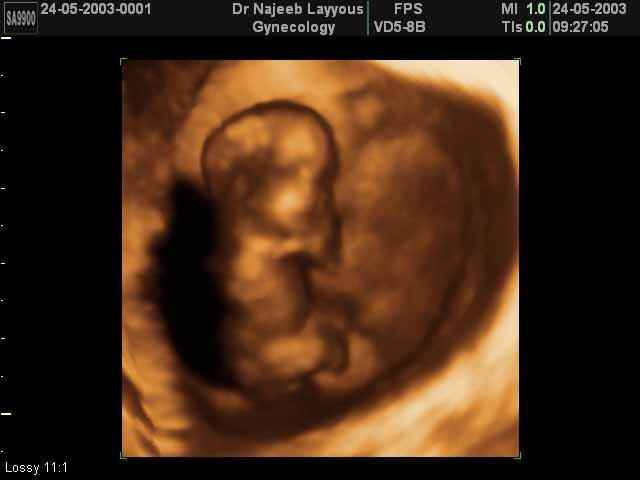

- First Trimester Ultrasound Photos

3D First Trimester Ultrasound Scan Photos ( Early Pregnancy Ultrasound Photos ) | Dr N Layyous